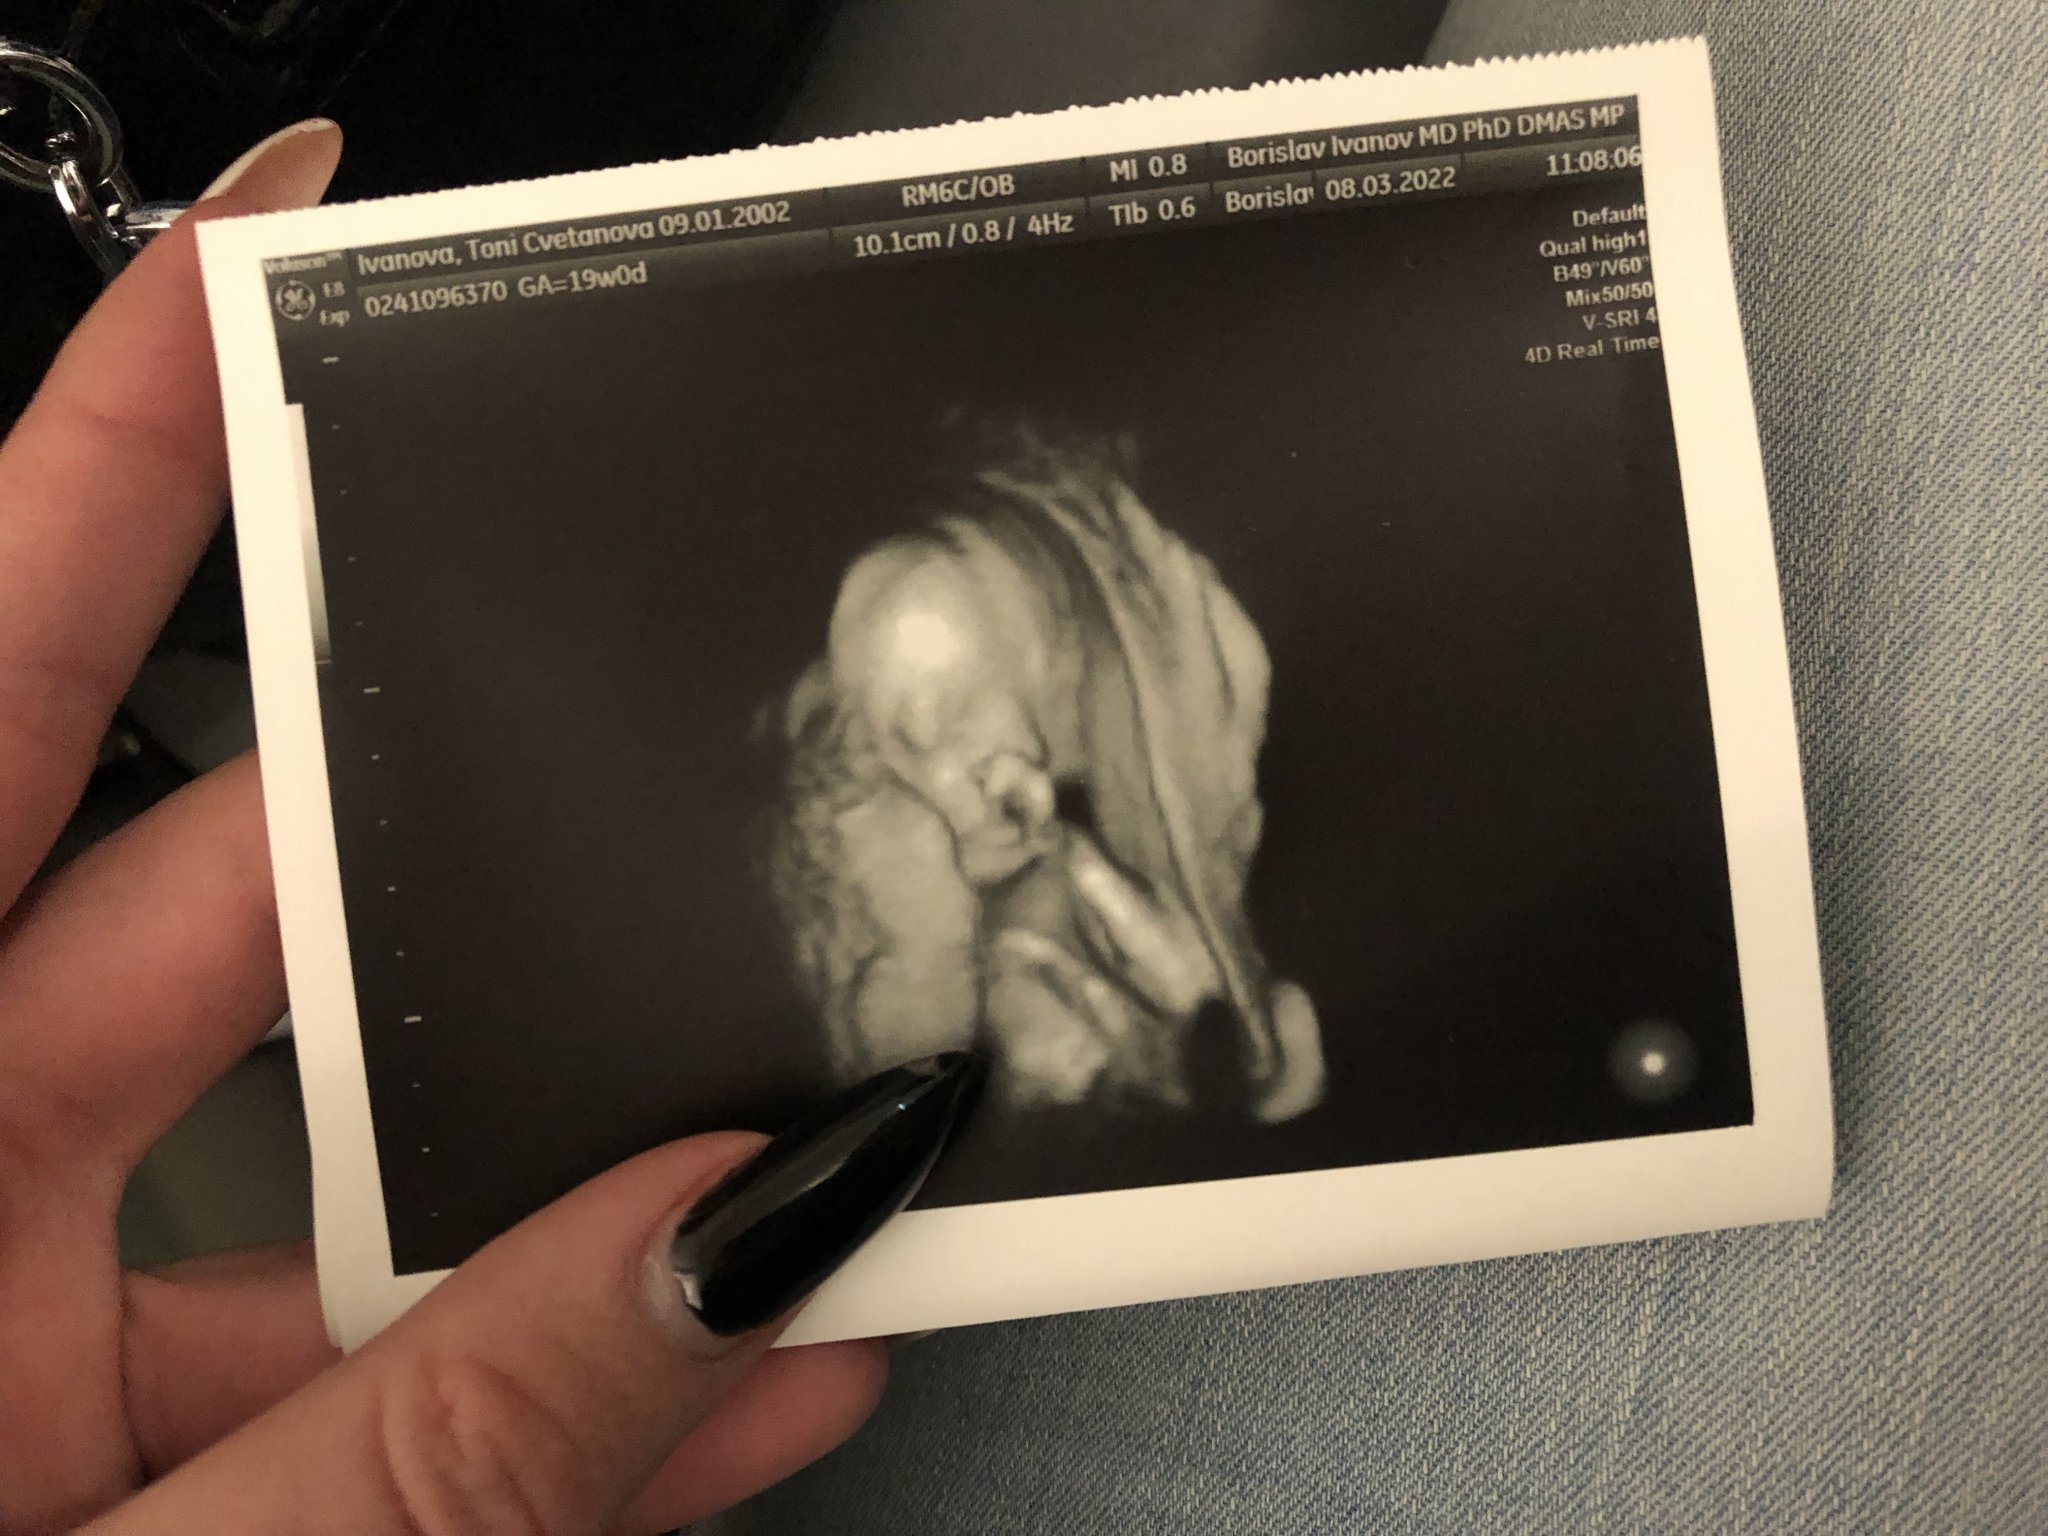

Кога обикновено започват да се усещат движенията на бебето?

Усещането на движенията на бебето може да варира от жена до жена. Повечето жени започват да ги чувстват около 18-20 седмица, но при някои това може да се случи и по-късно, особено при първа бременност. Намаленото усещане за ритничета може да се дължи на позицията на бебето, като например когато е обърнато с гръб. Важно е да се доверите на съвета на вашия лекар и да споделите всички притеснения с него.